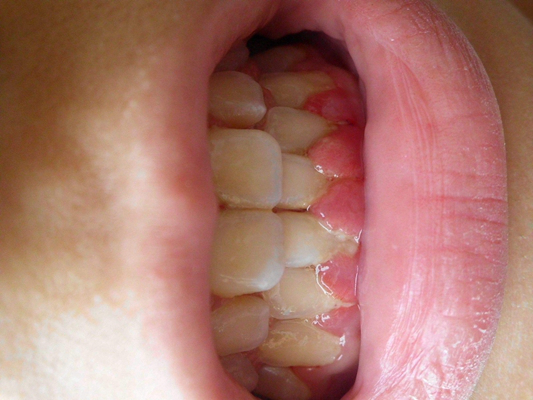

牙齦炎圖片

牙齦炎和牙周炎